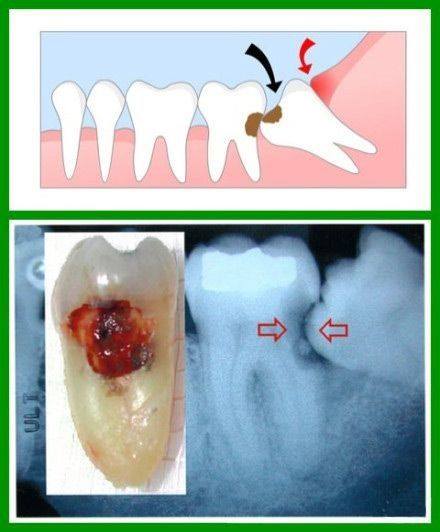

Periodontal Disease and Wisdom Teeth David C. Stahr, DDS Oral Surgery …

Pericoronitis | Wisdom Teeth | Dentist Orange West Haven Woodbridge CT

Operculectomy | Exodontia